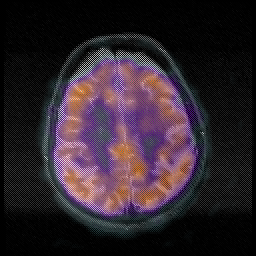

Huntington's Chorea, MR -- Slice #15

[Home][Help][Clinical] Slice 15